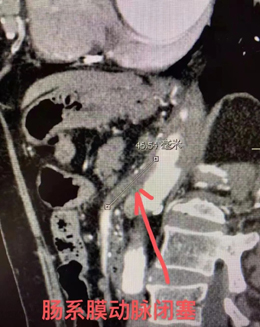

入院后在积极给予营养支持的前提下,血管外科对腹腔大血管进行了三维重建,结果令医生大吃一惊!老人重要器官供应血管均发生了严重狭窄或闭塞,供应肠道的两大动脉:肠系膜上动脉和肠系膜下动脉完全闭塞,供应肝脏和脾脏的动脉完全闭塞,供应肾脏的肾动脉严重狭窄,供应大脑的颈动脉严重狭窄,甚至供应下肢的髂动脉也存在严重狭窄。如何解决这样多处重要分支血管问题,解决的顺序又当如何,以及如何才能在治疗过程中保障老人全身机能的稳定?这些艰巨的挑战摆在血管外科医生面前。

介入治疗对于血管外科的医生来说早已轻车熟路,穿刺置管造影一气呵成,髂动脉球囊扩张支架植入、肾动脉球囊扩张支架植入在按部就班地进行。按照以往处理肠系膜动脉的经验,动脉开口只要有一点显影,都有机会介入开通,但是,最不愿看到的事情还是发生了,肠系膜上动脉一点都没有显影,而这根动脉是术前判断的导致老人腹痛的罪魁祸首。怎么办?肠系膜动脉不能恢复血流,患者的腹痛就不能缓解,老人的就诊目的无法实现。刘建龙主任当机立断,不再考虑保守治疗,准备开腹行血管搭桥。